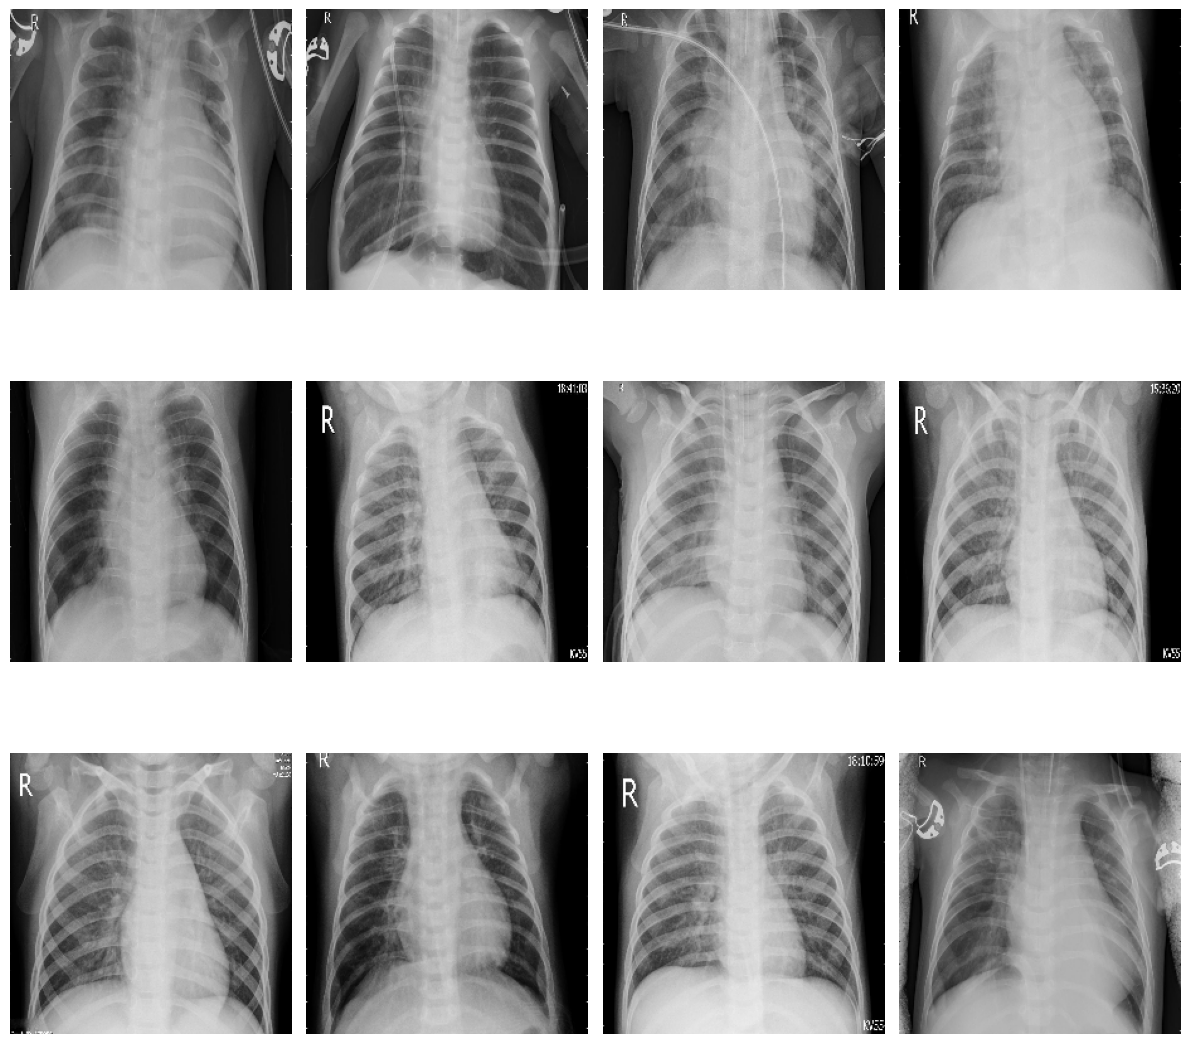

plot_samples(test_pneumonia, 12, 3, 4, save_as="train_samples_pneumonia.png")

../_images/train_samples_pneumonia.png

Samples of sick patients in training data